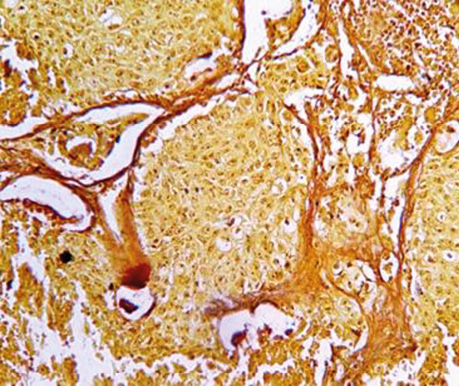

Отже, детальне вивчення гістологічної структури плоскоклітинного і залозистого РЛ дозволило виявити в кожному препараті 30 хворих ділянки БАРЛ, тобто тих місць, з яких починається ріст РЛ від базальної мембрани альвеоли і продовжується до її центру. Такий напрямок росту пухлини можна оцінити за допомогою не тільки морфологічних ознак клітин, характеру їх забарвлення, але і за результатами імуногістохімічних реакцій. Використані нами моноклональні антитіла Ki-67 і PCNA, за допомогою яких можна виявити ступінь проліферації клітин, зумовили позитивну реакцію в клітинах базальних шарів і негативну в тих екземплярах, які ростуть над ними і наближалися до центру альвеол, вони були більш зрілими і з ознаками розпаду (див. рис. 5). У результаті виконаних досліджень можна констатувати, що морфологічні ознаки, напрямок росту ракових клітин в альвеолах і підтвердження їх проліферативної активності росткової зони імуногістохімічними дослідженнями дають привід вважати СК (АТІІ) істинними зародковими центрами РЛ.

Рис.5. Залозистий рак. Розпад пухлинних клітин у центрі альвеоли, відділення пухлинних клітин від солідної структури праворуч. Гематоксилін і еозин. Збільшення ×1000